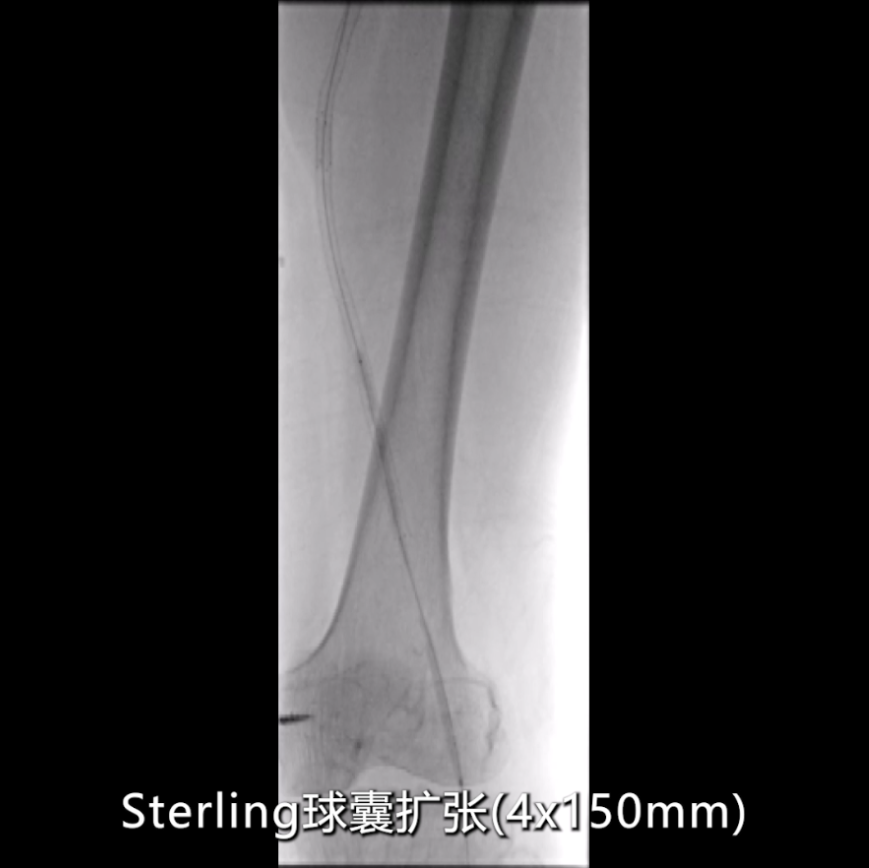

球囊扩张成形

初步扩张:使用4×150mmSterling球囊,由近及远扩张整个支架段及远端病变(考虑合并P1段病理性改变);

在影像图下发现在在支架远端有一定的局部狭窄。